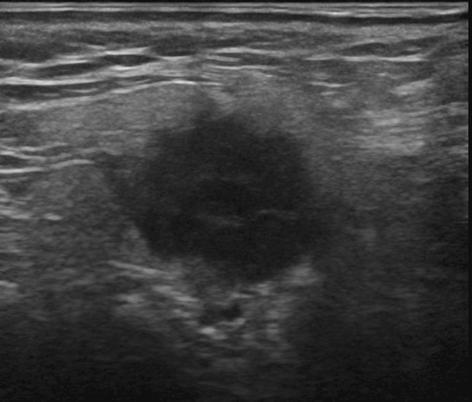

U tuyến nước bọt

U tuyến nước bọt - Ảnh 4

» Thông tin: Nam giới – 72 tuổi.

» Lâm sàng: Khối vùng mang tai.

# Ung thư biểu mô tuyến (Adenocarcinoma).